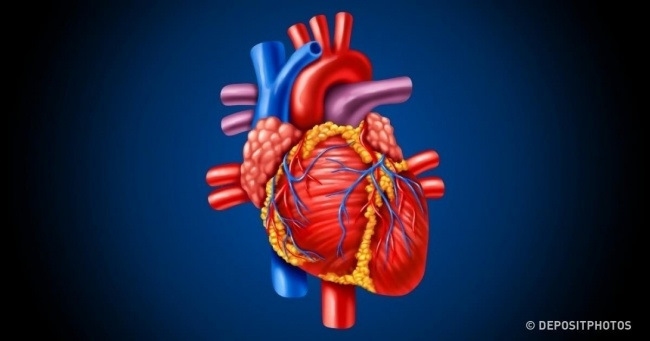

Анатомия здорового сердца: фотографии и иллюстрации